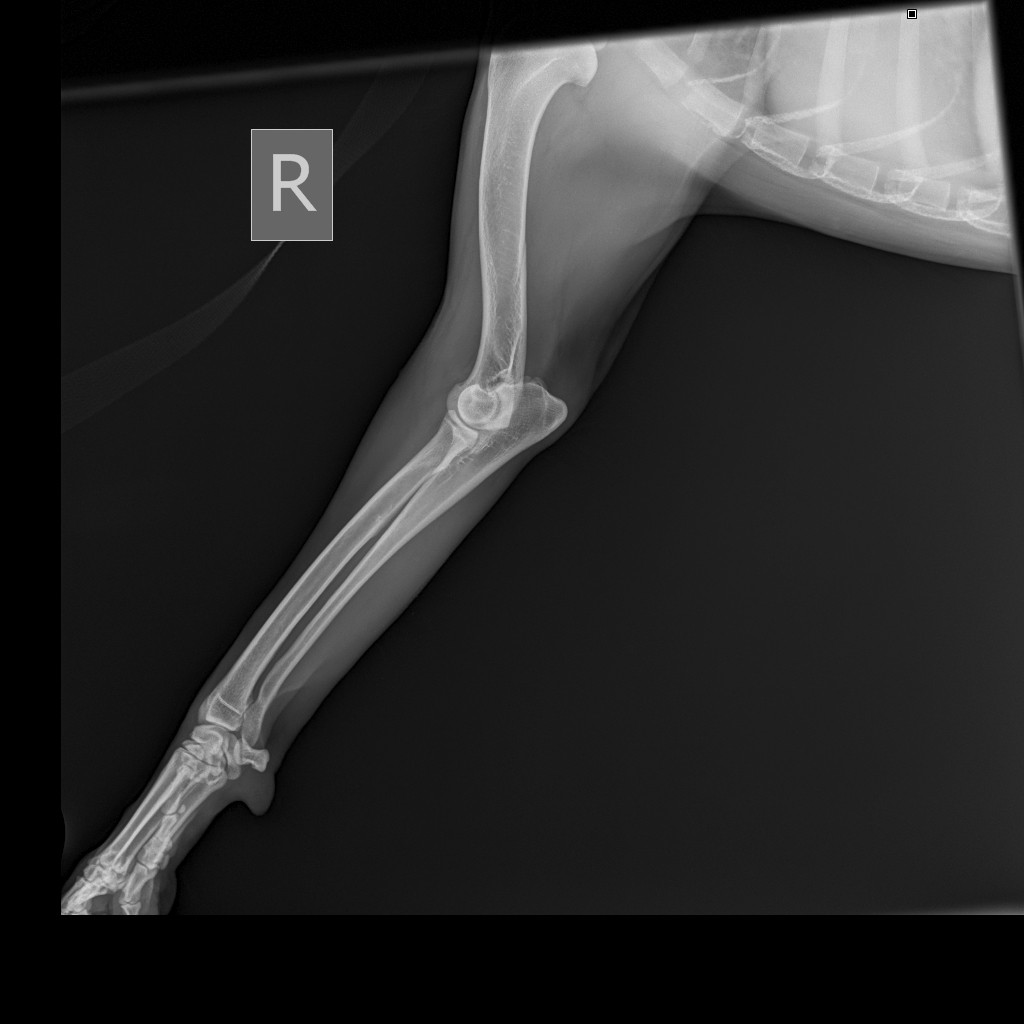

На обзорной рентгенограмме скелета левой передней конечности определяется:

Признаки мелких остеофитов на суставной поверхности запастья. Локтевой сустав без видимых изменений.

На обзорной рентгенограмме скелета правой передней конечности определяется:

Заключение: R-признаки артроза запястных суставов грудных конечностей.